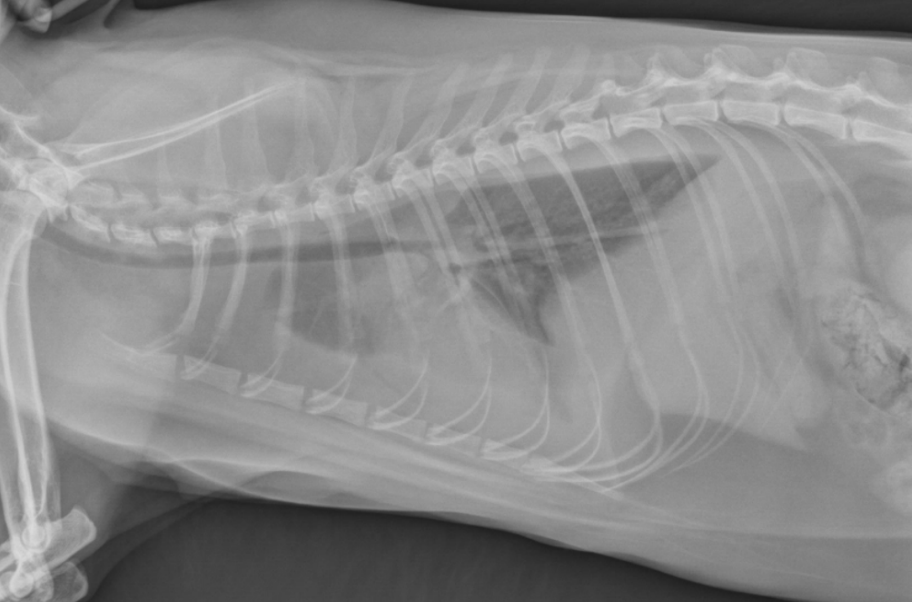

● 12 yo dog

● Coughing for 2 months

alveolar pattern caudodorsally (black tree visible)

fat in ventral thorax

cardiac silhouette lifted and rounded, maybe free fluid

on VD: mass effect